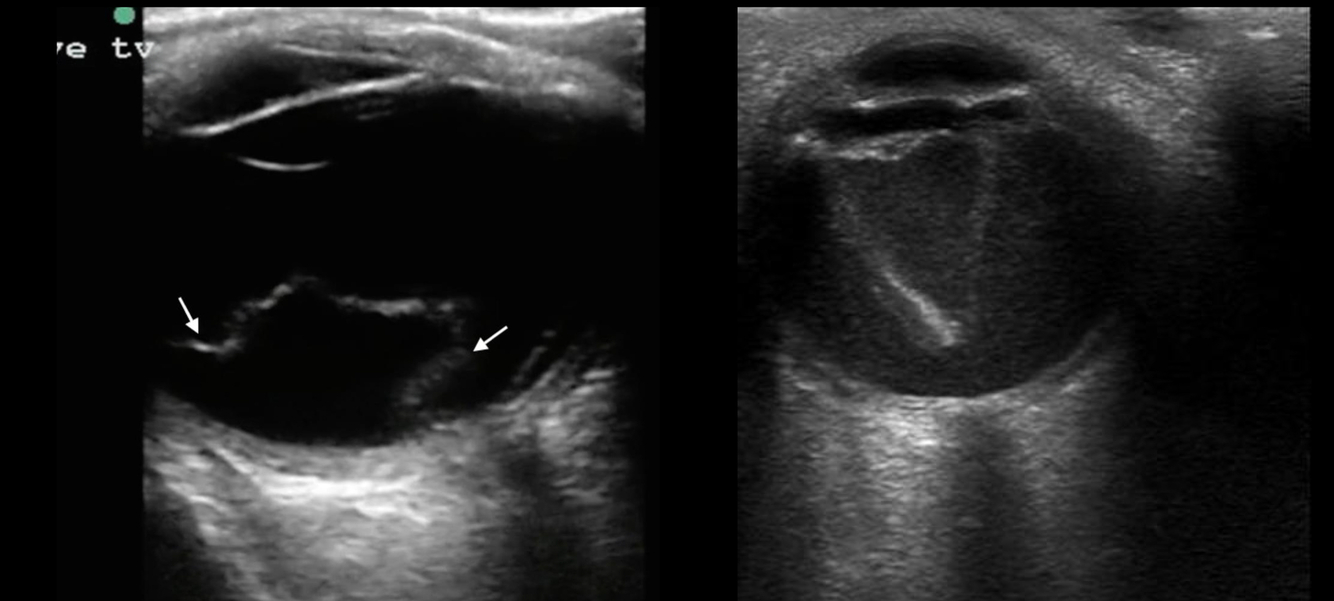

16

Q

Qué es?

A

US de desprendimiento de retina

Retina doblada y brillante

Forma triangular